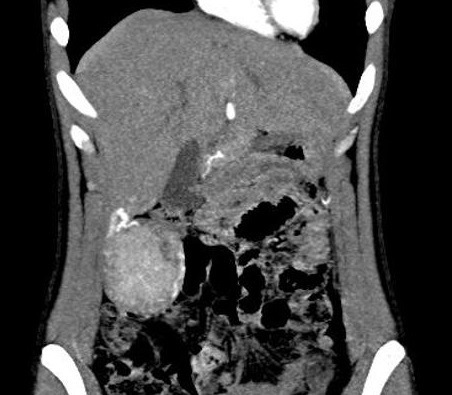

Multiple adenome du foie

: Images arrondies ou ovalaire , bord regulier a

hypodense situe au foie droit . Image radiologique

TDM du foie (n'a pas de contrast ) en coupe axiale |

Meme cas en coupe TDM axiale

du foie , phase arteriel : Image de

rehaussement important et precoce sur zone non

necrotique apres une injection de contrast

intraveineuse |

Meme cas en

phase portale . Aspect lesionaire |

Adenome du foie : Image de lesion

hypodensse avec rehaussement des zones anecrotique

du foie droit . Coupe axiale TDM du foie avec IPDC |